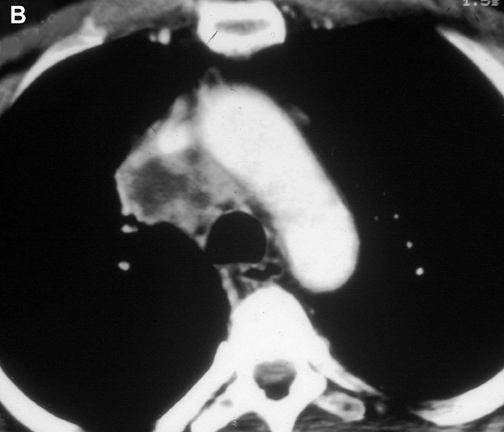

The anatomy of the SVC (Figure 1) and left brachiocephalic vein put this venous system in a critical area vulnerable to tumors arising both in the lung and anterior mediastinum. Malignant invasion is the most frequent indication for SVC resection and reconstruction. Lung cancer can involve the vessel with direct invasion by primary tumors arising in the right upper lobe or by nodal metastases (stations R2, R4 and 3) (Figure 2). Anterior mediastinal tumors (thymoma, thymic carcinoma, germ cell tumors, etc) may involve directly both the SVC and the left brachiocephalic vein (Figure 3). Primary tumors of the SVC represent a rare indication for surgery. Other infrequent indications are saccular aneurysms or primary malformations and traumatic lesions (iatrogenic, blunt, or penetrating injuries).

| Figure 2A & B. (A) Lung cancer invading the superior vena cava. (B) Mediastinal lymph nodes invading the superior vena cava. | Figure 3. Cortical thymoma invading the superior vena cava. | |